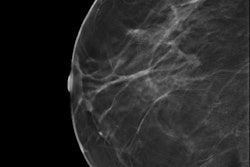

The combination of digital mammography (DM) plus digital breast tomosynthesis (DBT) finds 90% more breast cancer than digital mammography alone -- and with a similar recall rate, according to a study published online on 5 June in Radiology.

The combination of the two modalities found 8.6 cancers per 1,000 cases -- almost twice the rate of digital mammography alone, at 4.5 per 1,000 cases. The recall rate was 3.5% in both the combination and the digital mammography alone groups.